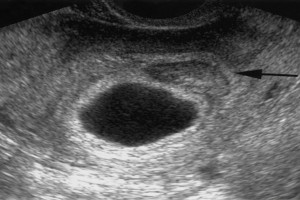

Diplomados en Ultrasonografía